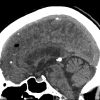

Mỡ nội sọ

Mỡ nội sọ - Ảnh 2

» Thông tin: Nam giới – 46 tuổi.

» Lâm sàng: Kiểm tra sức khỏe.